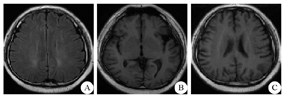

A:FLAIR序列显示脑白质脱髓鞘改变;B、C:T1序列显示皮质萎缩,脑裂、脑沟增宽

男,35岁,因"四肢末端麻木3月,语无伦次、行走不稳3 d"于2017年7月1日入辽宁省人民医院神经内科。该患者自半年前起出售充"笑气"的安瓿并间断吸充入该气体的"气球",具体吸入量不详。该患者3月前出现肢体麻木感,未予系统治疗,3 d前在自家轿车里被家人发现吸入"笑气",患者当时呈欣快感,傻笑,答非所问,小便失禁,行走不稳,但未见抽搐、饮水呛咳及吞咽障碍。病程中无发热,无呕吐。病来3 d未入睡。该患者既往"口吃",否认神经精神疾病及消化系统疾病病史,否认"笑气"以外其他精神活性物质接触史。入院体检:体温36.2 ℃,脉搏81次/min,呼吸18次/min,血压101/61 mmHg (1 mmHg=0.133 kPa)。肥胖体型、眼周晦暗、心肺听诊未闻及明显异常。神经系统查体:意识恍惚、言语笨拙(口吃),颅神经查体未见确切异常。四肢肌张力正常,可见四肢自主活动,四肢腱反射对称叩出。左侧Babinski征阳性。无脑膜刺激征,感觉体检不配合。入院后予以佐匹克隆及奥拉西坦治疗。入院第3天患者神志清,但反应迟钝,计算力(100-7=?)及远近期记忆力差,理解力、定向力正常,双上肢及双下肢近端肌力5级,双下肢远端肌力4级。Romberg征阳性,双下肢音叉振动觉与位置觉对称存在,四肢末端痛觉迟钝。左侧Babinski征仍阳性。简易智能状态检测量表(MMSE)评分18分。化验肝肾功、血糖、血脂、尿便常规、梅毒螺旋体抗体、凝血功能、叶酸、甲功、凝血功能、脑脊液生化及常规检测均未见明显异常。化验维生素B12示135 pg/mL (正常值211~911 pg/mL);同型半胱氨酸示65 μmol/L (正常值3.7~13.9 μmol/L);血常规示红细胞计数4.22×1012/L [正常值(4.3~5.8)×1012/L],血红蛋白、红细胞平均体积、血小板及白细胞计数均正常;钙2.10 mmol/L [正常值(2.15~2.5)×1012/L];尿酸508 μmol/L(正常值:214~488 μmol/L);壁细胞抗体、内因子抗体及胃泌素分泌细胞抗体检测均为阴性。肝胆脾胰超声检查示脂肪肝,肺CT、心电图、心脏超声、泌尿系统超声、颈部血管、锁骨下动脉超声检查、颈髓及胸髓MRI均未见明显异常。电子纤维胃镜示慢性非萎缩性胃炎。双侧胫神经神经传导速度(NCV)减慢,波幅正常。头MRI检查示双侧侧脑室旁、半卵圆中心稍长T1、稍长T2信号,FLAIR呈高信号改变,脑裂、脑沟增宽(图1)。患者出现精神异常、智力障碍、锥体束及周围神经等广泛损害,结合患者有N2O接触史,考虑为N2O中毒性脊髓病(亚急性联合变性)及中毒性脑病。家属拒绝高压氧治疗,予以腺苷钴胺(1.5 mg/d、1次/d,肌注)、奥拉西坦(4.0 g、1次/d,静点)及佐匹克隆(7.5 mg、1次/d,睡前口服)等治疗11 d,患者行走不稳较入院时缓解,计算力(86-7=?)及近期记忆力改善,双下肢远端肌力达4+级。MMSE量表评分21分,遂予以出院。出院后继续口服甲钴胺(0.5 mg、3次/d)及胞磷胆碱(0.2 g、3次/d),并配合康复治疗,3个月后复查,患者肢体麻木感消失,可正常行走,神经系统查体未见确切定位体征,MMSE量表评分28分。

大多数吸食者会通过小灯泡、面具或气球来吸入N2O,从而产生飘飘欲仙的致幻快感。吸入的N2O仅以物理状态溶解于血液中,不与血红蛋白结合,绝大多数以原形随呼吸排出体内,只有少量经皮肤蒸发,微量会在尿道或肠道中经肠道细菌的生物作用分解为氮和亚硝酸盐等,并随尿液、粪便排到体外。急性N2O中毒或高浓度N2O可以引起低血压、肺损伤导致缺氧窒息等。通常吸入N2O 15~30 s即可产生欣快感,但只能持续2~3 s。由于N2O造成的"欣快感"持续时间很短,吸食者会反复吸入,根据道尔顿的分压定律,吸食了大量的"笑气"之后,同一时间内吸到肺里的氧气就会相应减少,长期持续吸入就会导致缺氧,继而出现高血压、心脏病、晕厥等,严重者可有窒息的风险。另外,长期吸食N2O可以引起贫血及神经系统损害,严重的情况下会造成精神异常,如精神错乱、抑郁或嗜睡等,甚至导致死亡[3]。目前国外已报道了20余例滥用N2O导致的脊髓损伤,大多数与滥用N2O病例后引起维生素B12缺乏有关[4]。国内王丽等[5]也对此做了相关报道,N2O造成的脊髓损伤表现为脊髓亚急性联合变性的症状与体征,MRI特点是病变集中在颈髓和胸髓后索呈不规则的白质脱髓鞘,可能向前外侧及上下扩展,T2WI显示脊髓后索倒"V"形高信号是其典型的影像学特征。该患者头MRI表现为皮质萎缩、脑白质脱髓鞘等影像学特点,而脊髓MRI未出现上述特征,考虑与患者接触"笑气"时间短、病变较轻,大脑对缺氧更为敏感等有关。

维生素B12又称钴胺素,是机体反应所必须的辅助因子。长期或大剂量滥用N2O,会影响维生素B12的合成,因为N2O可以氧化维生素B12中的钴离子,使其成为其他钴胺素类似物,并被优先排出体内,从而引起维生素B12缺乏并失活,再经过快速抑制蛋氨酸合成酶活性,使甲基丙二酰辅酶A变位酶(MCM)减少等一系列酶促反应,导致巨幼红细胞性贫血或髓鞘脱失。正常情况下,当体内有大量的维生素B12储备时,应用N2O进行麻醉不会引起上述临床症状,通常仅发生于有潜在维生素B12缺乏的患者中[6]。Duque等[4]认为N2O在肠道中被维生素B12还原为氮气,随之生成的羟基自由基可以使蛋氨酸合成酶失活从而导致髓鞘合成和代谢障碍。有研究认为N2O可以改变抗γ-氨基丁酸A型受体(GABAAR)、抗N-甲基-D-天冬氨酸受体(NMDAR)、5-羟色胺受体(5-HTR)和阿片受体等功能,产生包括神经元坏死和细胞凋亡的神经损害[7]。该患者头MRI示脑白质脱髓鞘及皮质萎缩,考虑除与上述机制有关外,还可能与长期吸入N2O导致脑部中枢神经系统处于缺氧状态有关。